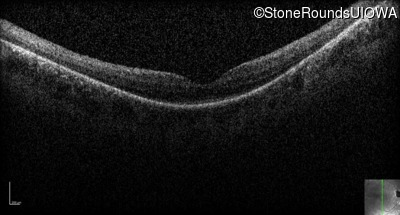

Optical Coherence Tomography - Left - 20/80 -2

Exemplar / OCT Stack

OCT Stack